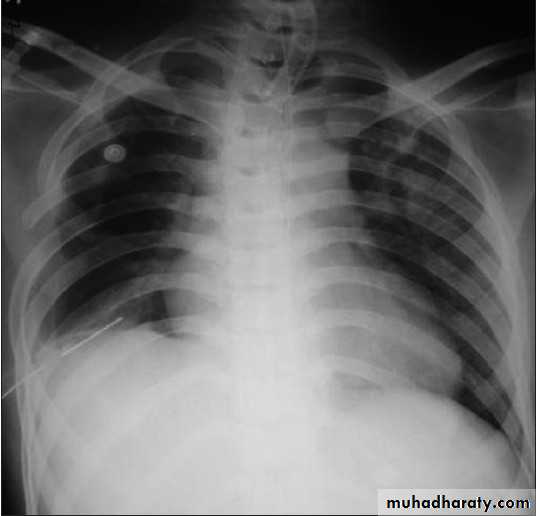

• Check up chest x-ray

Severe dyspnea with shock